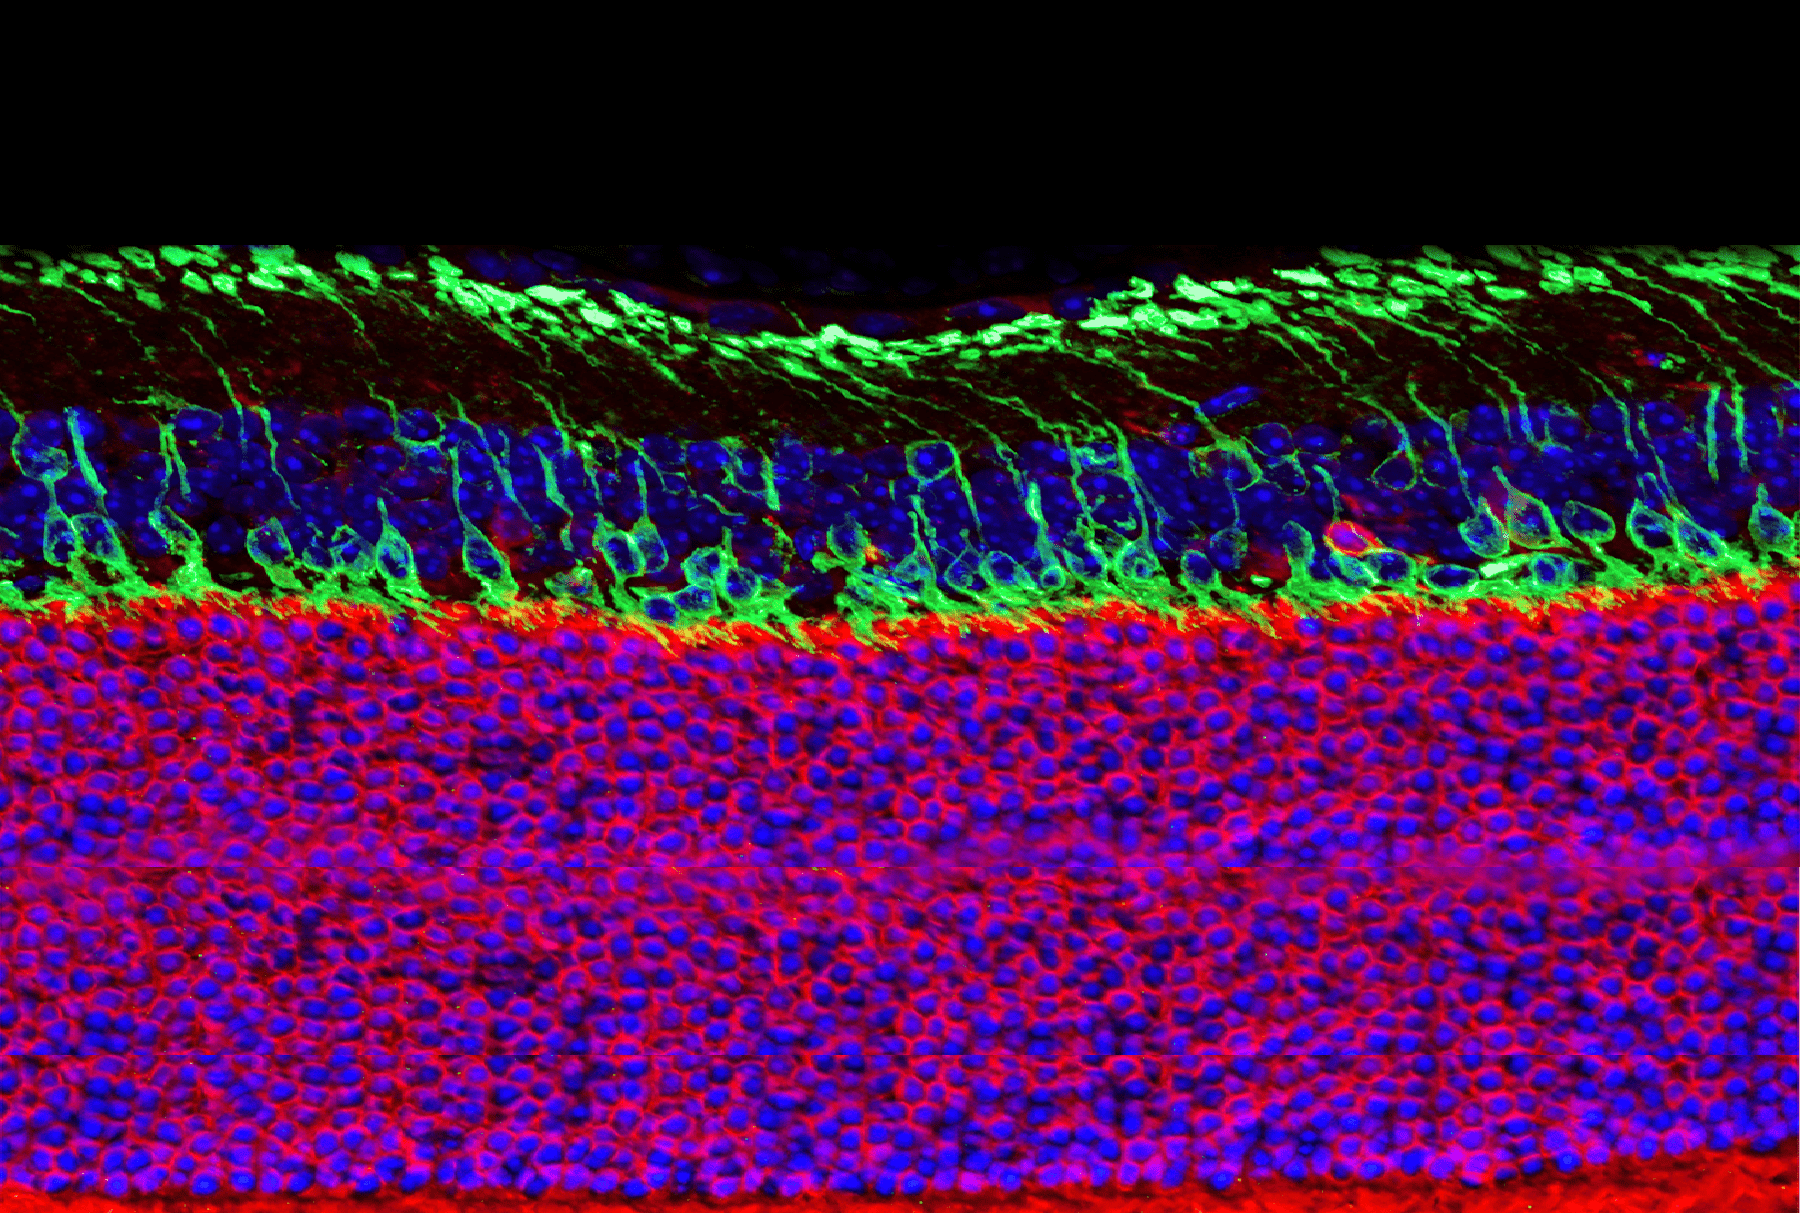

Background: The availability of in vitro models of the human retina in which to perform pharmacological and toxicological studies is an urgent and unmet need. Most drug studies are performed in vivo in experimental animals, but this approach is far from optimal because there are fundamental, structural, and functional differences between the rodent and human retina. The advent of organoid technology has made possible the generation of three-dimensional (3D) self-organised laminated and light-responsive retinal organoids from pluripotent stem cells (PSCs), a powerful tool for disease modelling and drug discovery. However the lack of microglia and vasculature currently limits their utility in two ways: firstly, it is known that microglia and vasculature play an important role in retinal development and disease, and secondly, the vascular system is necessary to prevent formation of necrosis in tissues that grow beyond 500µm diameter because of impaired diffusion of oxygen and nutrients. The vascular cells in the retina interact closely with the retinal neurons and glial cells, forming the retinal neurovascular unit (NVU), which together with the retinal pigment epithelium (RPE) form the core of the blood retina barrier (BRB). The BRB mediates highly selective diffusion of molecules from the blood to the retina and maintains retinal homeostasis. Alterations of the BRB play a crucial role in the development of retinal diseases, thus dynamic modelling of human BRB in highly desirable.

Aims and Objectives: Current conventional co-culture models of retinal organoids with endothelial and microglia cells bypass the developmental processes that lead to formation of spatially organised retinal NVU and BRB. Furthermore, the mesodermal origin of microglia and vascular cells, and ectodermal origin of neural retina, provide a significant barrier for the generation of vascularised immunocompetent retinal organoids incorporating NVU/BRB. Our aim is to reach beyond the state of the art to combine multiple organoid types in 3D culture to generate vascularised immunocompetent retinal assembloids that combine the neural and mesodermal cells and provide all the components of retinal NVU/BRB.

Methods: We will generate PSC-vascular organoids that contain endothelial cells, pericytes, smooth muscle and microglia and assemble those with cardiac and retinal organoids to make vascular immune competent functional retinal assembloids. We will employ a combination of molecular (immunofluorescence confocal microscopy, single cell RNA-Seq) and functional (retina light response, assembloids perfusion, BRB permeability, microglia activation) to fully characterize the assembloids.